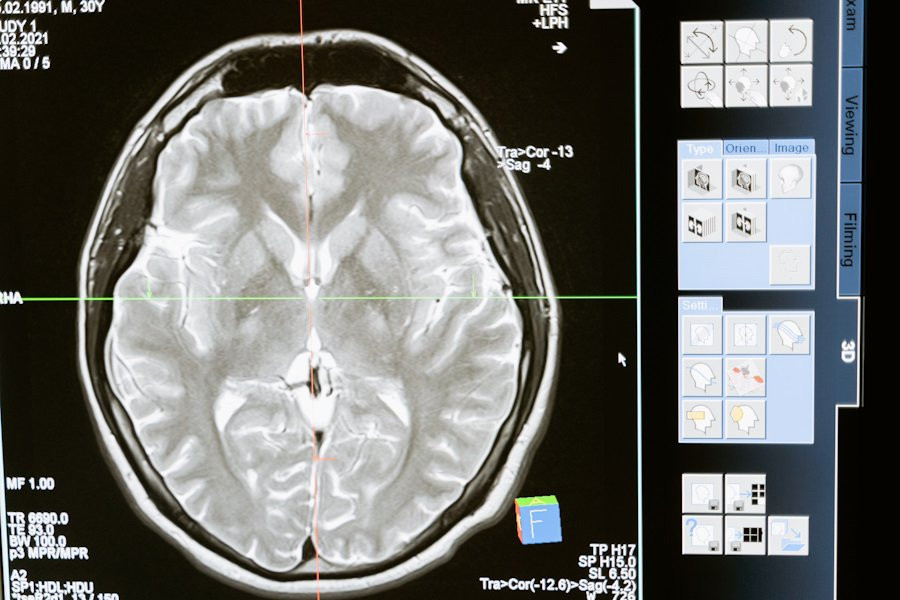

Исследователи из Institute for Basic Science (IBS) (Республика Корея) провели успешные испытания новой методики Magnetogenetic Interface for NeuroDynamics (Nano-MIND), которая позволяет воздействовать на мозг человека без использования имплантатов. Эта технология объединяет магнитные поля и намагниченные наночастицы, что открывает новые возможности для нейромодуляции, сообщает портал Nature.

На сегодняшний день наиболее распространенными методами управления нейронной активностью являются оптогенетика и глубокая стимуляция мозга. Оптогенетика использует свет для активации клеток мозга, а глубокая стимуляция мозга применяется, например, для лечения болезни Альцгеймера. Однако оба метода требуют использования имплантатов.

Технологии нейромодуляции играют ключевую роль в исследовании связей и функций мозга. Магнитная нейромодуляция предлагает беспроводную и удаленную глубокую стимуляцию мозга, что делает её уникальной по сравнению с оптогенетикой и проводными электродами. Ранее использование магнитных подходов было ограничено из-за недостаточного понимания их работы и плохо спроектированных систем.

Методика Nano-MIND использует намагниченные наночастицы и технологию Cre-loxP для избирательной активации генетически закодированных ионных каналов Piezo1 в целевых популяциях нейронов. Это позволяет точно контролировать активность нейронов глубокого мозга как in vitro, так и in vivo.